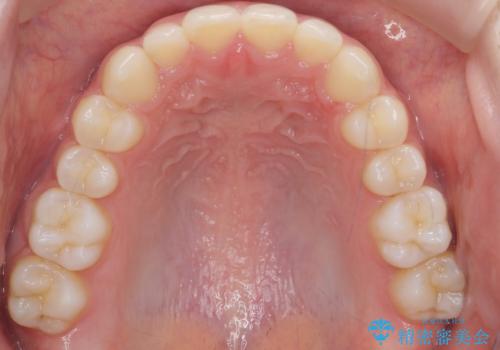

前歯のガタつき・ねじれを治すマウスピース矯正

マウスピース矯正を始める前にワイヤー部分矯正を行ったことで改善のしにくい歯のねじれをしっかりと治すことができました。

- 前歯のねじれ、ガタつきを改善し綺麗な歯並びにしたいと希望され来院されました。